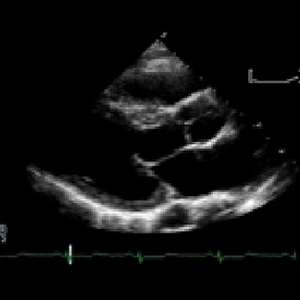

Examines your overall heart function. Over 60% of the general populate has valvular heart disease. Approximately 40% of the population over 50 years old has diastolic dysfunction.